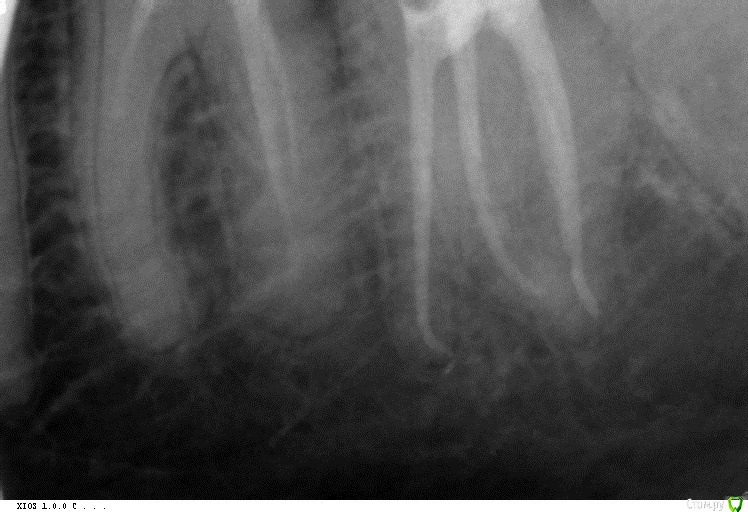

Audutor Опубликовано 13 июля, 2016 Поделиться Опубликовано 13 июля, 2016 Protaper SX,S1,S2. Profile 0.4,0.6. Protaper Hand use.Финишировать всегда стараюсь Protaper Hand use F3 насухо, под контролем апекс локатора. Ссылка на комментарий

cor Опубликовано 14 июля, 2016 Поделиться Опубликовано 14 июля, 2016 Для меня F3 - слишком большое расширение устьевой и средней трети. Что бы я его засунул в канал - это исключение. Меня, как и остальных, интересует апикальная треть, а именно, как добиться адекватной ирригации в ней, родимой. Можно послушать Каплана, а можно взять эндоблок, и посмотреть (Каплан, блин, прав). Протейперы, в их классическом применении не дадут Вам возможности отмыть апикальную треть, не "убивая" анатомию канала. Но протэйперы быстро и эффективно работают в других отделах канала. А именно в устьевой и средней трети.Дальше можно подключить другие инструменты. Будь то профайлы, а может и К-3. Готовясь к "тапкам" опубликую ленивый протокол. Он работает только с опытом его использования, и пониманием, зачем)) По протоколу до протейпера F2, 30.06 профайл (35.04,40.04, 45.04 - по ситуации). Обязательно апикальный упор (калибровка гутты обязательна, только "2 конус). Ну и опыт в таких "экспериментах" заканчивался латералкой. Было здорово. Но попробуйте на удалёнках сначала, а то Мяуздрав предепреждает)) Ссылка на комментарий

St. Опубликовано 14 июля, 2016 Поделиться Опубликовано 14 июля, 2016 Готовясь к "тапкам" опубликую ленивый протокол. Он работает только с опытом его использования, и пониманием, зачем)) По-хорошему любой протокол будет работать, если понимаешь что и зачем делаешь) А так вполне логично, но я бы остановилась на протейперах С1 и С2, а дальше неагрессивно - или профайлы или К3 1 Ссылка на комментарий

St. Опубликовано 14 июля, 2016 Поделиться Опубликовано 14 июля, 2016 Протейперами работала пару лет в формате С1, С2, Ф1, дальше руками калибровать апикально.К3 и профайлами тоже работала по класической схеме.Совмещение первых и вторых по-моему логично в не сильно изогнутых каналах: первые быстро расширят устье и середину,практически не расширяя апикально, а вторые исключительно апикально и будут работать. Нагрузка на инструмент будет меньше, расширение достаточное, и по времени быстрее чем просто неагрессивными. Ссылка на комментарий